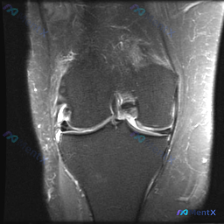

膝盖MRI发现半月板异常,别漏了这个更严重的问题!

病例影像分析分享 今天拿到这张膝盖冠状位T2加权MRI,核心问题是半月板异常,整理了完整的分析思路和大家分享。 基本影像信息 本次提供的是膝关节冠状位T2加权MRI序列,先给大家整理系统性读片结果: 1. 骨骼结构:股骨远端、胫骨近端骨皮质连续,内侧间室可见异常信号改变,本序列无法评估隐匿性骨挫伤...